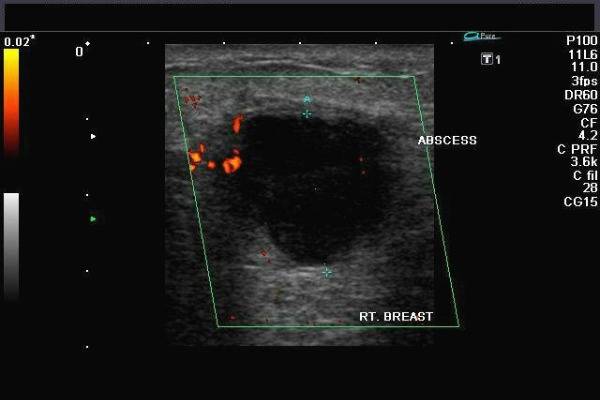

К сожалению, медсестры хорошо справляются только с «расцеживанием», но в некоторых случаях этого может быть недостаточно или, наоборот, противопоказано. Например, при мастите очень важно определить, есть ли гнойные абсцессы. Самолечение и попытки «расцедить» такие абсцессы приводят к очень печальным последствиям. Опасно также то, что при гнойном мастите, несмотря на наличие гнойных полостей (абсцессов), температура тела может быть нормальной, и это нередко воспринимается «самолечащимся» пациентом как улучшение состояния и тенденция к выздоровлению.

Мастит. Присутствуют очаговые образования вблизи от ареолярного сегмента. Контуры ровные, структура однородная с незначительными усилениями. Рисунок выглядит затушеванным. На нем четко различимы гомогенные зоны с участками воспаления. При наличии гнойных очагов расширяются альвеолы и протоки, которые окружены инфильтратом, имеющим вид сот.

- При наличии гнойных маститов проведение УЗИ-процедуры исключено. Наличие воспалений на основе застоя молока подразумевает незамедлительное обращение к врачу, который предложит курс терапии и поможет избежать операции.